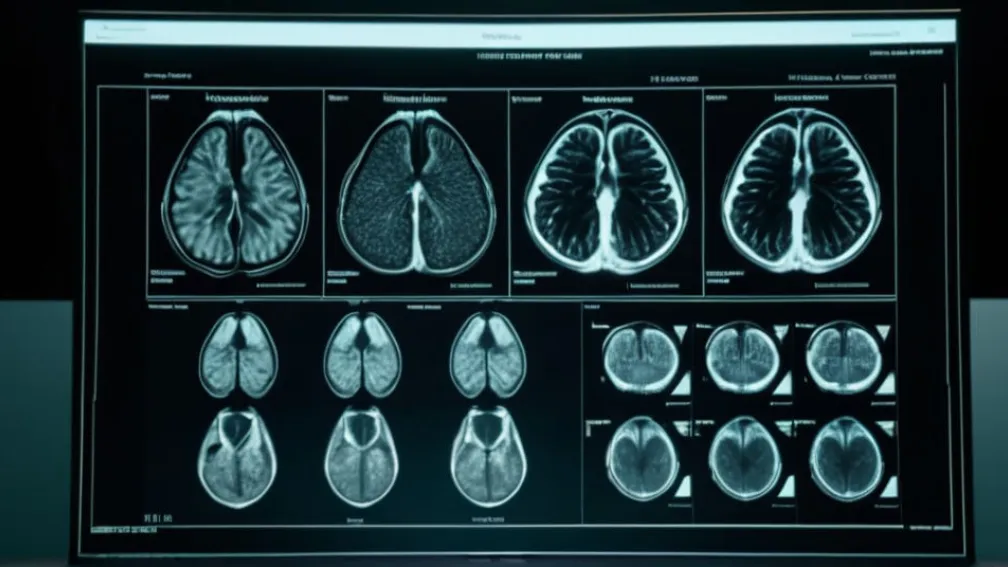

После недель спекуляций о состоянии здоровья бывшего президента США Дональда Трампа его личный врач, доктор Шон Барбабелла, опубликовал результаты магнитно-резонансной томографии (МРТ), проведенной в октябре.

Пресс-секретарь Белого дома Кэролайн Ливитт зачитала меморандум, в котором сообщалось, что МРТ брюшной полости Трампа не выявила никаких аномалий. В документе подчеркивалось, что "все основные органы выглядят очень здоровыми и хорошо кровоснабжаются".

"Все исследованные функции находятся в пределах нормы, без острых или хронических заболеваний. В целом, это детальное обследование соответствует стандартам медицинского осмотра для руководителей в возрасте президента Трампа и подтверждает, что он по-прежнему находится в отличном общем состоянии", — заявила Ливитт.

В меморандуме также отмечается "отличное" состояние сердечно-сосудистой системы. Ранее в этом году здоровье Трампа вызывало множество вопросов, особенно из-за сообщений об отеках лодыжек и загадочных пятнах на руке. В июле Белый дом сообщал, что президент страдает от "хронической венозной недостаточности".

Сам Дональд Трамп прокомментировал результаты как "идеальные" и, отвечая на вопросы журналистов на борту Air Force One, пошутил, что "не знает", какая часть его тела была отсканирована, но уточнил, что это был не мозг, так как он успешно прошел когнитивный тест.